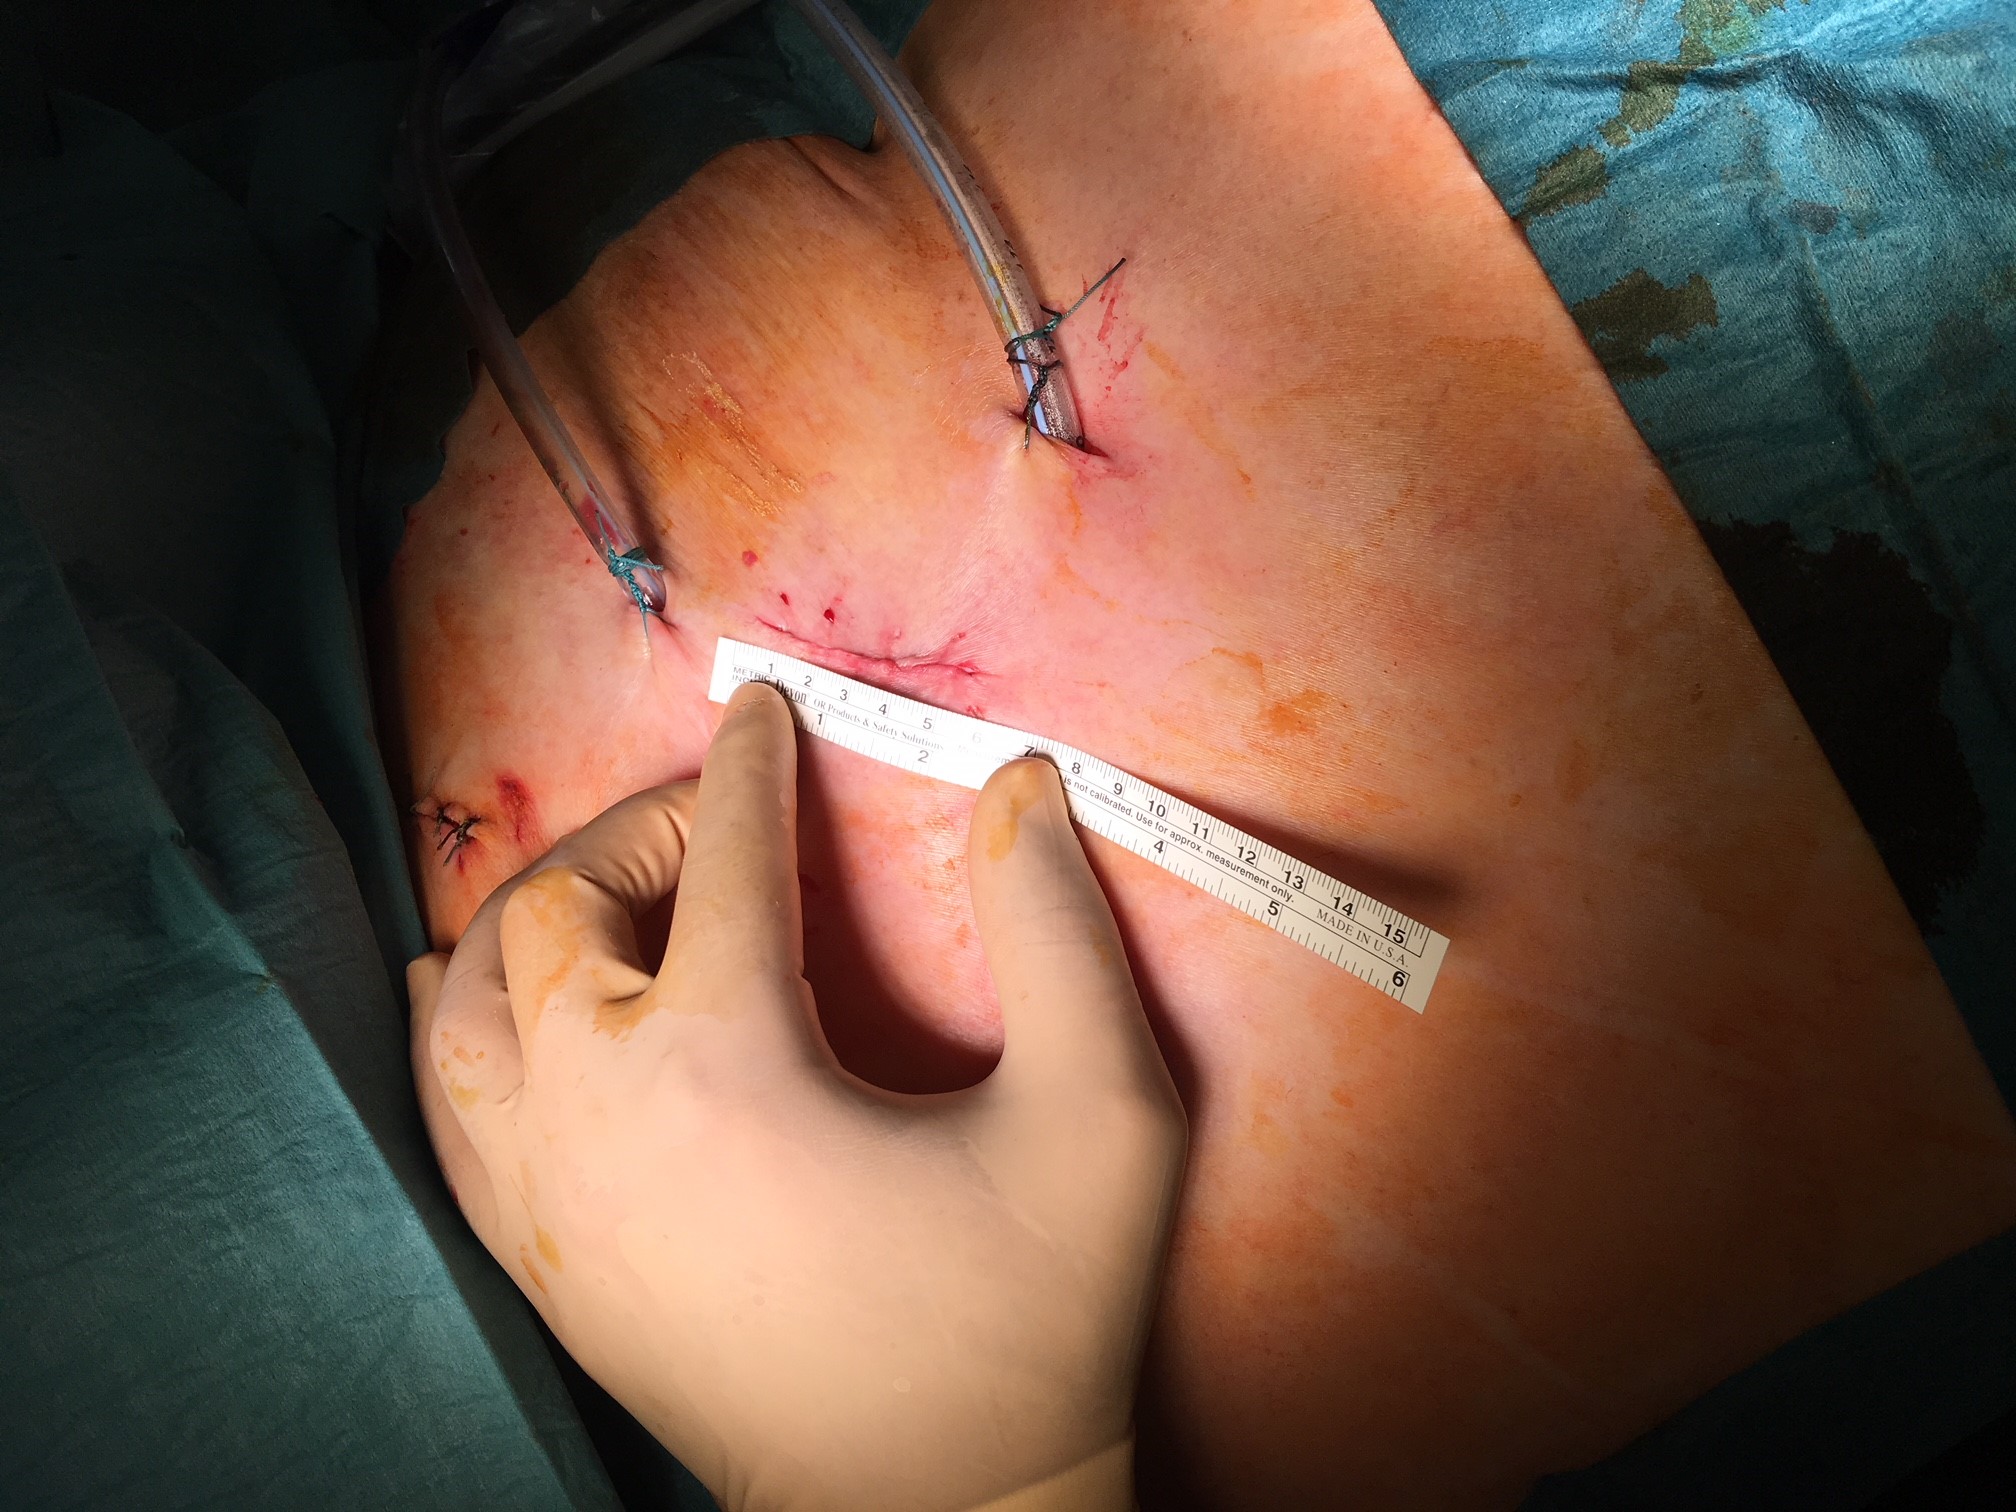

Für die Therapie verfügt unsere Klinik über die modernsten chirurgischen Techniken sowie die neuesten chirurgischen Geräte. Soweit möglich führen wir Eingriffe minimal-invasiv ("Schlüsselloch-Chirurgie") durch. Vorteile für den Patienten sind ein kürzerer stationärer Aufenthalt im Krankenhaus, eine schnellere Genesung und ein besseres kosmetisches Ergebnis.

Mit dem Begriff "minimal-invasive Thoraxchirurgie" werden Schlüsselloch-Techniken für Operationen bezeichnet, in der Thoraxchirurgie eine noch junge Methode, die sich rasant entwickelt. In unserer Klinik kann diese schonende Technik sogar bei der Therapie von Lungenkrebs zum Einsatz kommen.

Technisch hoch anspruchsvolle Lungenoperationen können in unserer Klinik auf endoskopische Weise videoassistiert vorgenommen werden (VATS: Video-assistierte Thoraxchirurgie). Die bei konventionellen Lungenoperationen notwendige Eröffnung des Brustkorbs mit einem großen Schnitt und mit Auseinanderspreizen der Rippen entfällt bei der VATS-Lobektomie. Die Patienten erholen sich wegen der sehr viel geringeren Wunde („Operationstrauma“) sehr viel schneller. Auch sind die durch die Operation hervorgerufenen Schmerzen deutlich geringer. Bei einer anatomischen Operation mit Lungenteilentfernung müssen die „Versorgungsleitungen“ durchtrennt werden, dies sind die Blutgefäße und die Luftröhrenäste. Diese Operationsschritte und mehr können endoskopisch vorgenommen und über Video-Übertragung am Monitor mit Vergrößerung durchgeführt werden. Die Technik der VATS–Lobektomie/Lappen-Resektion wird bei Frühstadien des Lungenkrebses erfolgreich eingesetzt wie auch bei einer Vielzahl anderer anatomischer Lungenoperationen (Segmentresektionen).

- kleine Narben (Kosmetik)

- weniger Schmerzen nach der Operation

- geringere Beeinträchtigung des Immunsystems

- kürzerer Krankenhausaufenthalt

- schnellere Genesung (Rekonvaleszenz) und damit Wiederaufnahme der Arbeit

- kleine Narben (Kosmetik)

- weniger Schmerzen nach der Operation

- geringere Beeinträchtigung des Immunsystems

- kürzerer Krankenhausaufenthalt

- schnellere Genesung (Rekonvaleszenz) und damit Wiederaufnahme der Arbeit

- besonders kleine Hautschnitte

- schnelle postoperative Erholung

- weniger Schmerzen

- kurzer stationärer Aufenthalt im Krankenhaus

- gutes kosmetisches Ergebnis